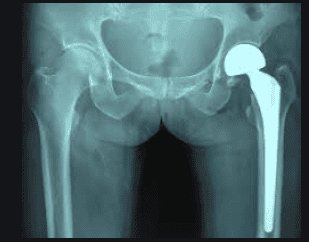

Thay khớp háng là một phương pháp phẫu thuật hiện đại cho những bệnh nhân mất chức năng khớp háng do tổn thương khớp háng gây ra. Nguy cơ trật khớp háng sau mổ chiếm khoảng 0,5-4% tùy thuộc vào kỹ thuật mổ và tình trạng bệnh kèm theo. Do phục hồi chức năng sau phẫu thuật rất quan trọng, là một quá trình từ trước khi phẫu thuật, sau phẫu thuật và đến khi ra viện. Phục hồi chức năng giúp cho bệnh nhân biết cách phòng tránh trật khớp háng tái phát.

Tóm lại, phục hồi chức năng sau phẫu thuật rất quan trọng, là một quá trình trước mổ, sau mổ và sau khi ra viện. Phục hồi chức năng giúp người bệnh phòng tránh tái phát sau phẫu thuật khớp háng, và thời gian phục hồi, trở lại hoạt động bình thường nhanh hơn. Ngoài ra, bệnh nhân cần tái khám định kỳ sau khi ra viện 1 tháng và 4 tháng. Sau đó cứ 6 tháng đến 1 năm phải kiểm tra lại khớp háng bằng X-quang để phát hiện kịp thời thoái hóa khớp háng.

Người bệnh cần chụp X-quang khớp háng định kỳ 6 - 12 tháng/lần để kiểm tra